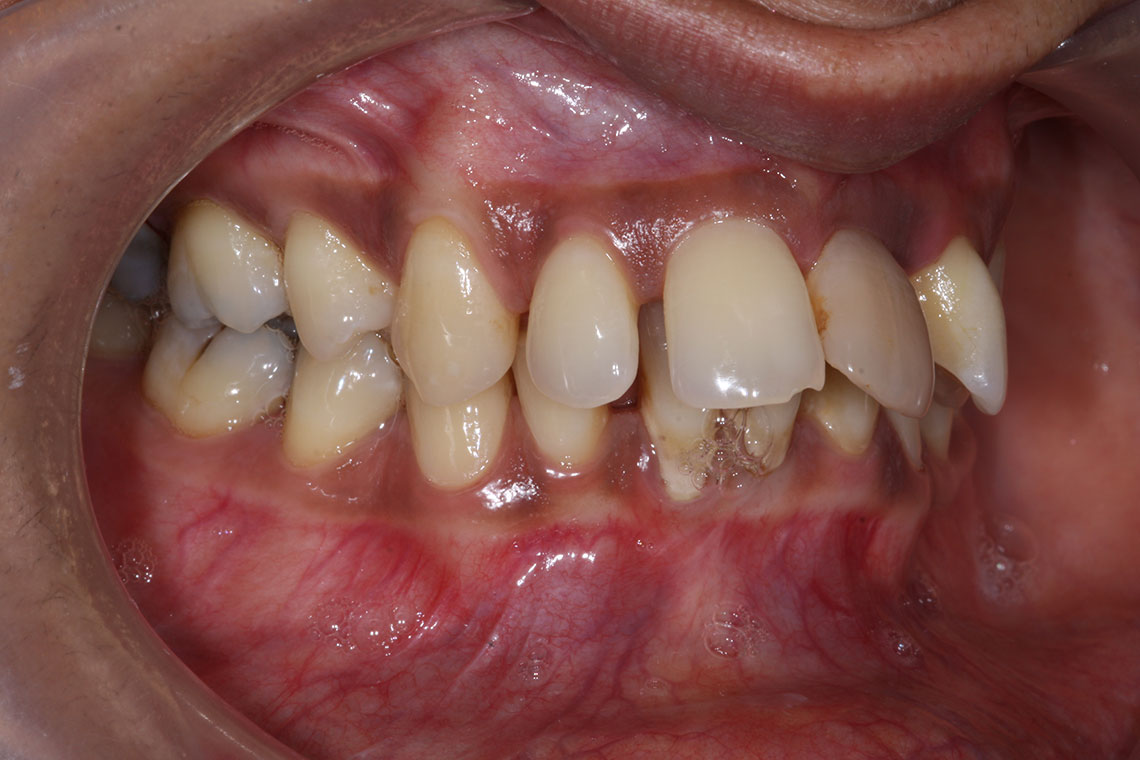

This lovely lady attended with very low confidence due to her teeth and smile. Gum disease and trauma had led to the teeth drifting. One of her front teeth was so loose that it needed to be replaced. We started by providing intensive treatment with our dental hygienist to treat the gum disease. Following this Invisalign® braces were used to align the teeth and the teeth were whitened. A dental implant was then placed to replace the loose front tooth and composite bonding was performed to the adjacent front tooth. The change in the patient’s confidence as a result of this work was breathtaking.